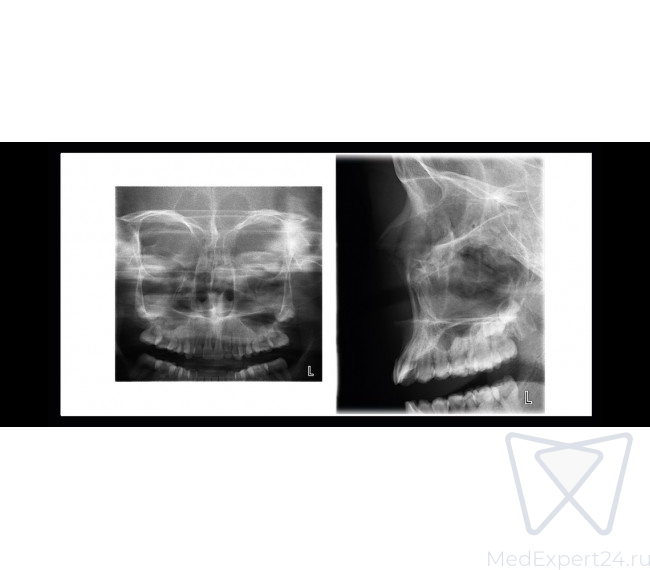

- Программа PA-вращающегося синуса,

- Задне-передние пазухи

- Задне-передние пазухи без вращения